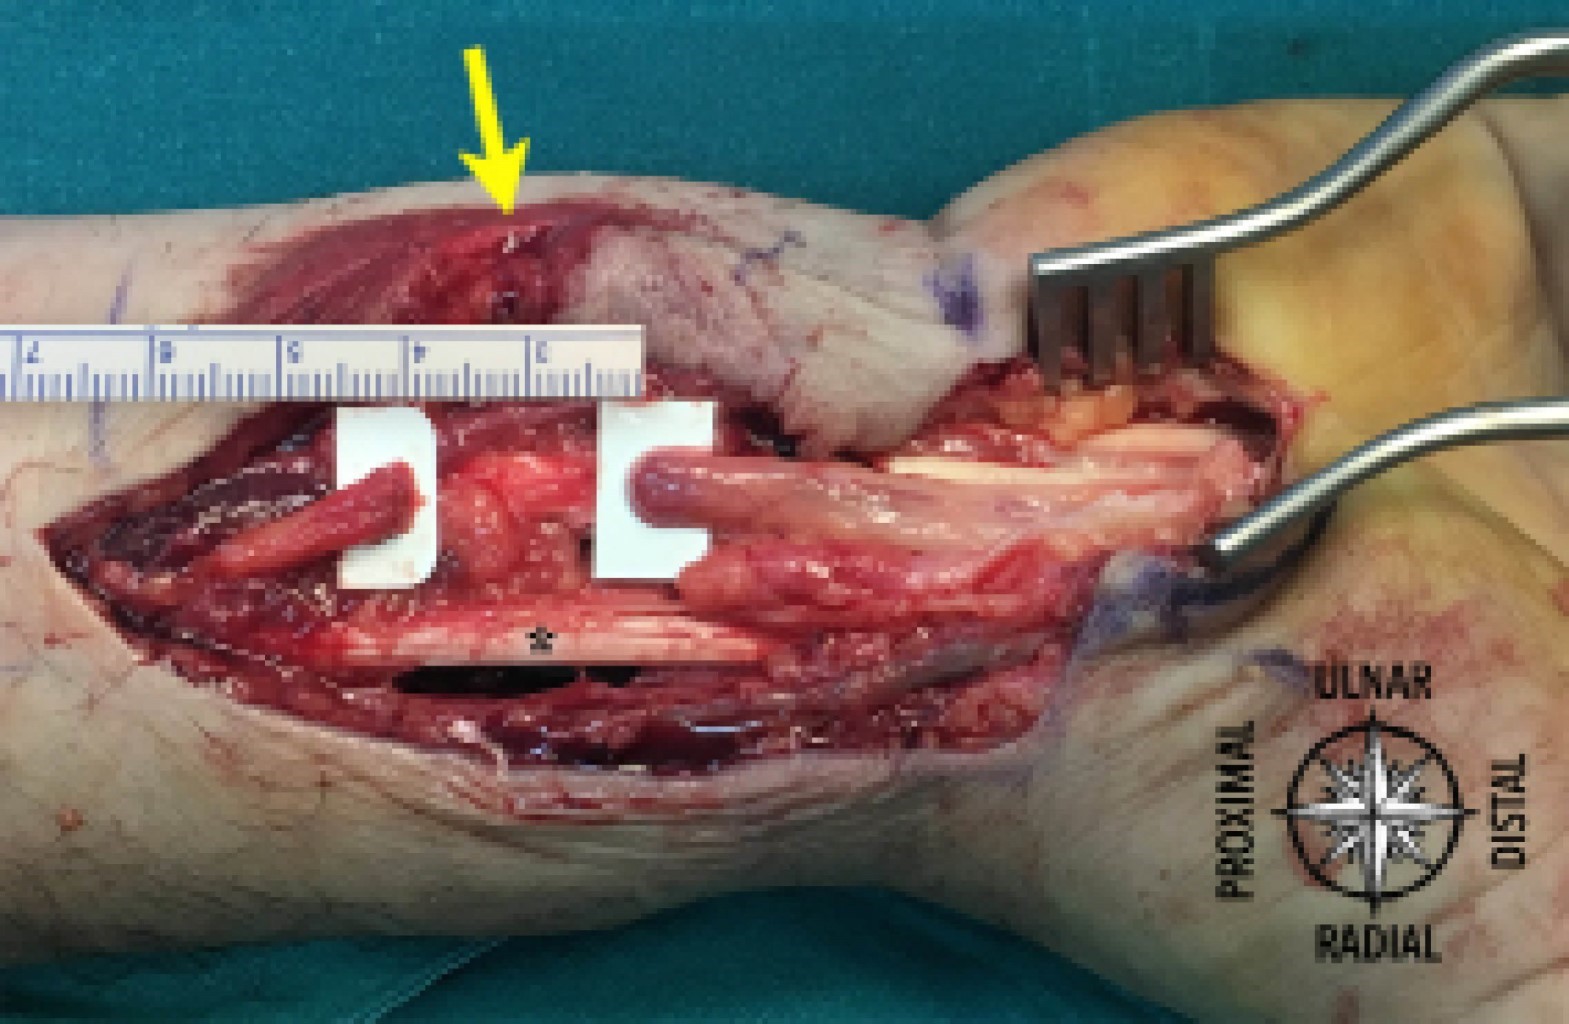

Introducción: las fracturas desplazadas de extremo distal del radio se acompañan frecuentemente de manifestaciones clínicas sugestivas de neuropatía del nervio mediano. El diagnóstico diferencial debe incluir la contusión o lesión nerviosa directa, el síndrome del túnel carpiano agudo, el síndrome compartimental del antebrazo o la exacerbación de un síndrome del túnel carpiano idiopático. Caso clínico: un varón de 44 años presentó una fractura del radio distal derecho tras un accidente de motocicleta. Presentaba una herida contusa de 1.3 cm situada proximalmente al pliegue de flexión radiocarpiano y refería disestesias bien definidas en el territorio sensitivo del nervio mediano. La fractura se trató mediante reducción abierta y osteosíntesis con placa volar y, por los hallazgos en la exploración inicial, se exploró el nervio mediano encontrando una sección completa con un defecto de 2.0 cm. Se liberó el túnel carpiano y se interpuso un injerto fascicular de nervio sural que presentó buenos resultados en el seguimiento final. Conclusión: la sección del nervio mediano tras una fractura de muñeca es una lesión extremadamente rara. Este caso clínico subraya la importancia de una exploración física inicial minuciosa incluyendo la evaluación neurológica inicial.

Figura 2